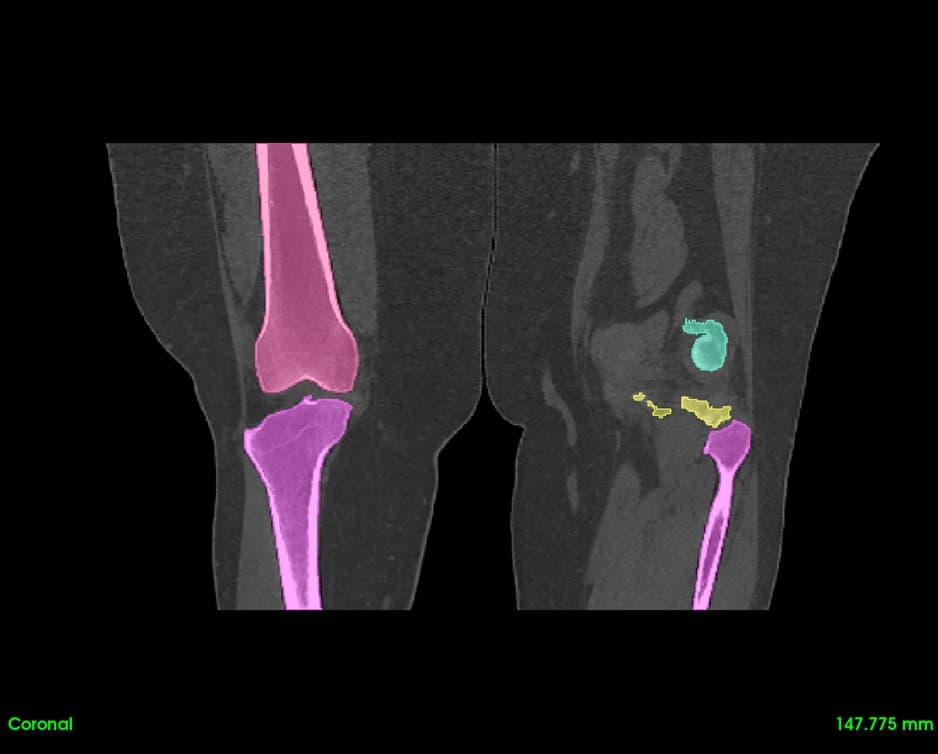

Segment bones, vasculature, and soft tissues with precision. User-friendly tools for accurate anatomical boundary delineation.

Real-time 3D rendering of segmented structures. Create patient-specific anatomical models for visualization and analysis.

Quickly visualize and analyze anatomical structures from CT and MRI scans. Identify abnormalities with precise 3D visualization.

Create patient-specific 3D anatomical models for pre-operative planning. Enhance surgical precision and patient outcomes.